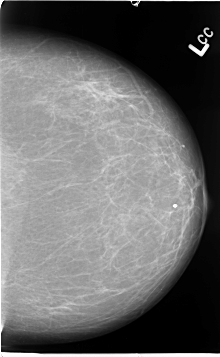

B_3067_1.LEFT_CC

LEFT_CC LINES 4632 PIXELS_PER_LINE 2848 BITS_PER_PIXEL 12 RESOLUTION 50 NON_OVERLAY

LEFT_MLO LINES 4656 PIXELS_PER_LINE 3136 BITS_PER_PIXEL 12 RESOLUTION 50 NON_OVERLAY